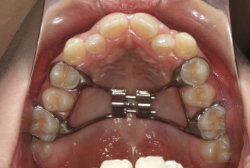

急速拡大装置を1日1回装置の中央にある拡大ネジを、ご自身で回して頂くことで25日間くらいかけて、6mmほど拡大しました。拡大後は、上顎の前歯の隙間が広がっていることがお分かりいただけると思うのですが、土台の骨ごと広がるのでこのような隙間ができます。その後1年半くらいマルチブラケット装置を使用して、全体の修正を行いました。

結局、歯の本数を減らすことなく、すべてご自分の歯を残して正しい配列にすることができました。このケースの場合、2009年10月より拡大と経過観察を行い、2012年3月より1年2ヶ月マルチブラケット装置を装着、2013年5月に治療を終了しました。2段階で行う治療としては短期間で終了しているケースと思います。